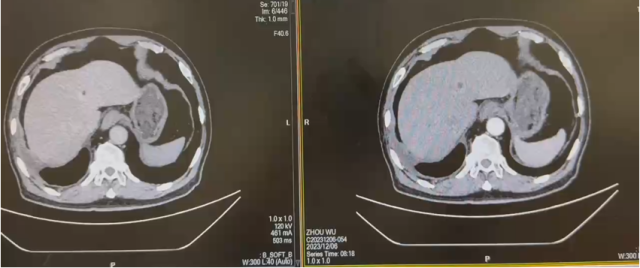

治疗后复查 CT(2022.7):左肾透明细胞 CA 治疗后改变,肿块较前缩小,强化程度减低,左侧副肾动脉可见;余况同前。

CT( 2024.4.26 ):1. 左肾 NSS 术后改变,左肾新见多发结节状等密度灶,考虑复发;2. 右输尿管上段结石消失,右肾积水缓解,右肾萎缩;3. 余况同前。

CT( 2024.12.5 ):1. 左肾 NSS 术后改变,左肾多发结节状等密度灶较前稍缩小;2. 右肾功能受损,同前相仿;3. 余况同前。

CT(2023.12.6):1. 左肾上腺结节较前稍缩小、左肾结节及肿块较前稍缩小;2. 腹膜后淋巴结转移灶同前;3. 余况基本同前。